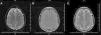

Further MRI scans of the brain 30 days after onset showed no abnormal findings on FLAIR, T2 and diffusion weight images (Figure 2) and the patient continued to be neurologically asymptomatic.